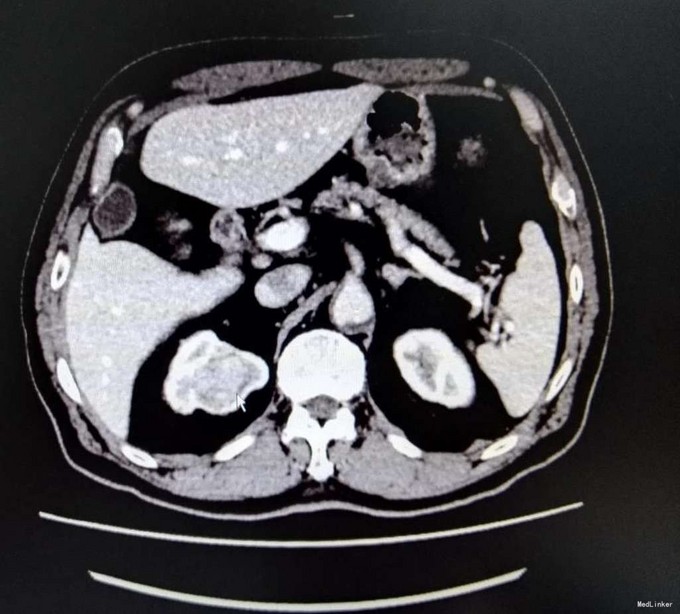

3、查体:无明显阳性体征 4、辅助检查:生化:肌酐:144umol/L。双肾CT平扫+增强:右肾上部肿块,考虑肾癌可能性大,ECT示:左肾 GFR 21.6ml/min,右肾GFR为22.3ml/min

5、肾癌 6、患者入院后完善相关检查,具体检查如上述,未见明显禁忌症,与患者及其家属充分沟通后,行腹腔镜下右侧肾癌根治术,术中未明显出血,术后患者恢复良好,术后病理提示肾透明细胞癌,患者顺利出院